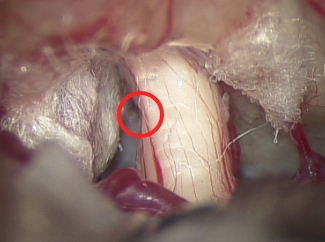

(写真2−前)三叉神経痛の患者さん(圧迫解除前)

白く見える三叉神経に血管がくいこむように強く圧迫し、神経が折れ曲がっています(緑矢印)

(写真2-後)三叉神経痛の患者さん(圧迫解除後)

圧迫の取れた三叉神経がまっすぐになっていることがわかります(赤丸が圧迫されていた場所)。周囲の血管は白く見えるテフロンの繊維で、二度と神経に当たらないように固定します。